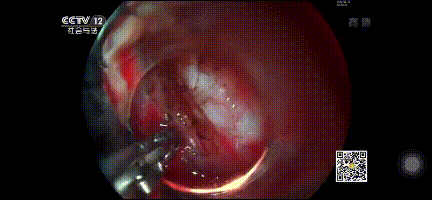

安瑞啄木鳥刀通過胃鏡進入,I刀環繞腫瘤通電標記,標記完成,I刀/O刀逐層剝離肌瘤。

標記